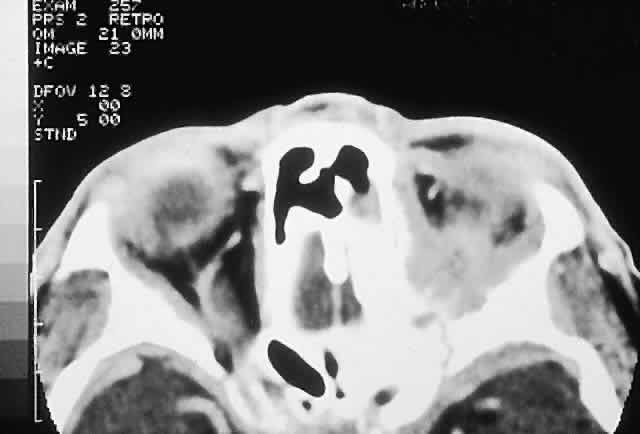

IMAGING. Chondrosarcomas appear as well-defined osteolytic lesions with stippled or mottled densities indicative of mineralization (Fig. 10). Higher-grade tumors tend to have irregular margins with nonuniform calcification in the form of amorphous cloudlike densities.125 The noncalcified regions show T1 signal intensities lower than or equal to gray matter on MRI. T2 signals are isointense to the cortex, and the masses usually display moderate enhancement.121,124,126,127

Fig. 10. This 46-year-old man with a history of midline chondrosarcoma resected 3 years previously presented with a right optic neuropathy. A. CT revealed recurrent tumor in the form of a heterogeneous mass involving both ethmoidal sinuses and orbit. Mottled areas of mineralization are apparent in the matrix of the lesion. B. The tumor was resected through an orbitocranial approach, and the histology revealed a grade 2 chondrosarcoma composed of hypercellular cartilage with lacunae containing binucleated chondrocytes (hematoxylin-eosin, × 50). He remains free of recurrence after 4 years.

HISTOPATHOLOGY. Grossly, the tissue is white to blue-gray, with a discernible lobular pattern. Histologically, there are irregular lobules of hypercellular cartilage with lacunae containing plump bi- or multinucleated chondrocytes, separated by fibrous stroma or reactive bony trabeculae. The stroma may be myxoid in areas and shows a wide variability in the amount of cellularity, atypia, and chondroid matrix, which has led to a grading system. The grades 1 through 3 appear to have some correlation with prognosis.119,121,128 This is manifest in tumors involving the orbit, which are mostly grades 1 or 2 and exhibit slow growth with a low incidence of metastasis.